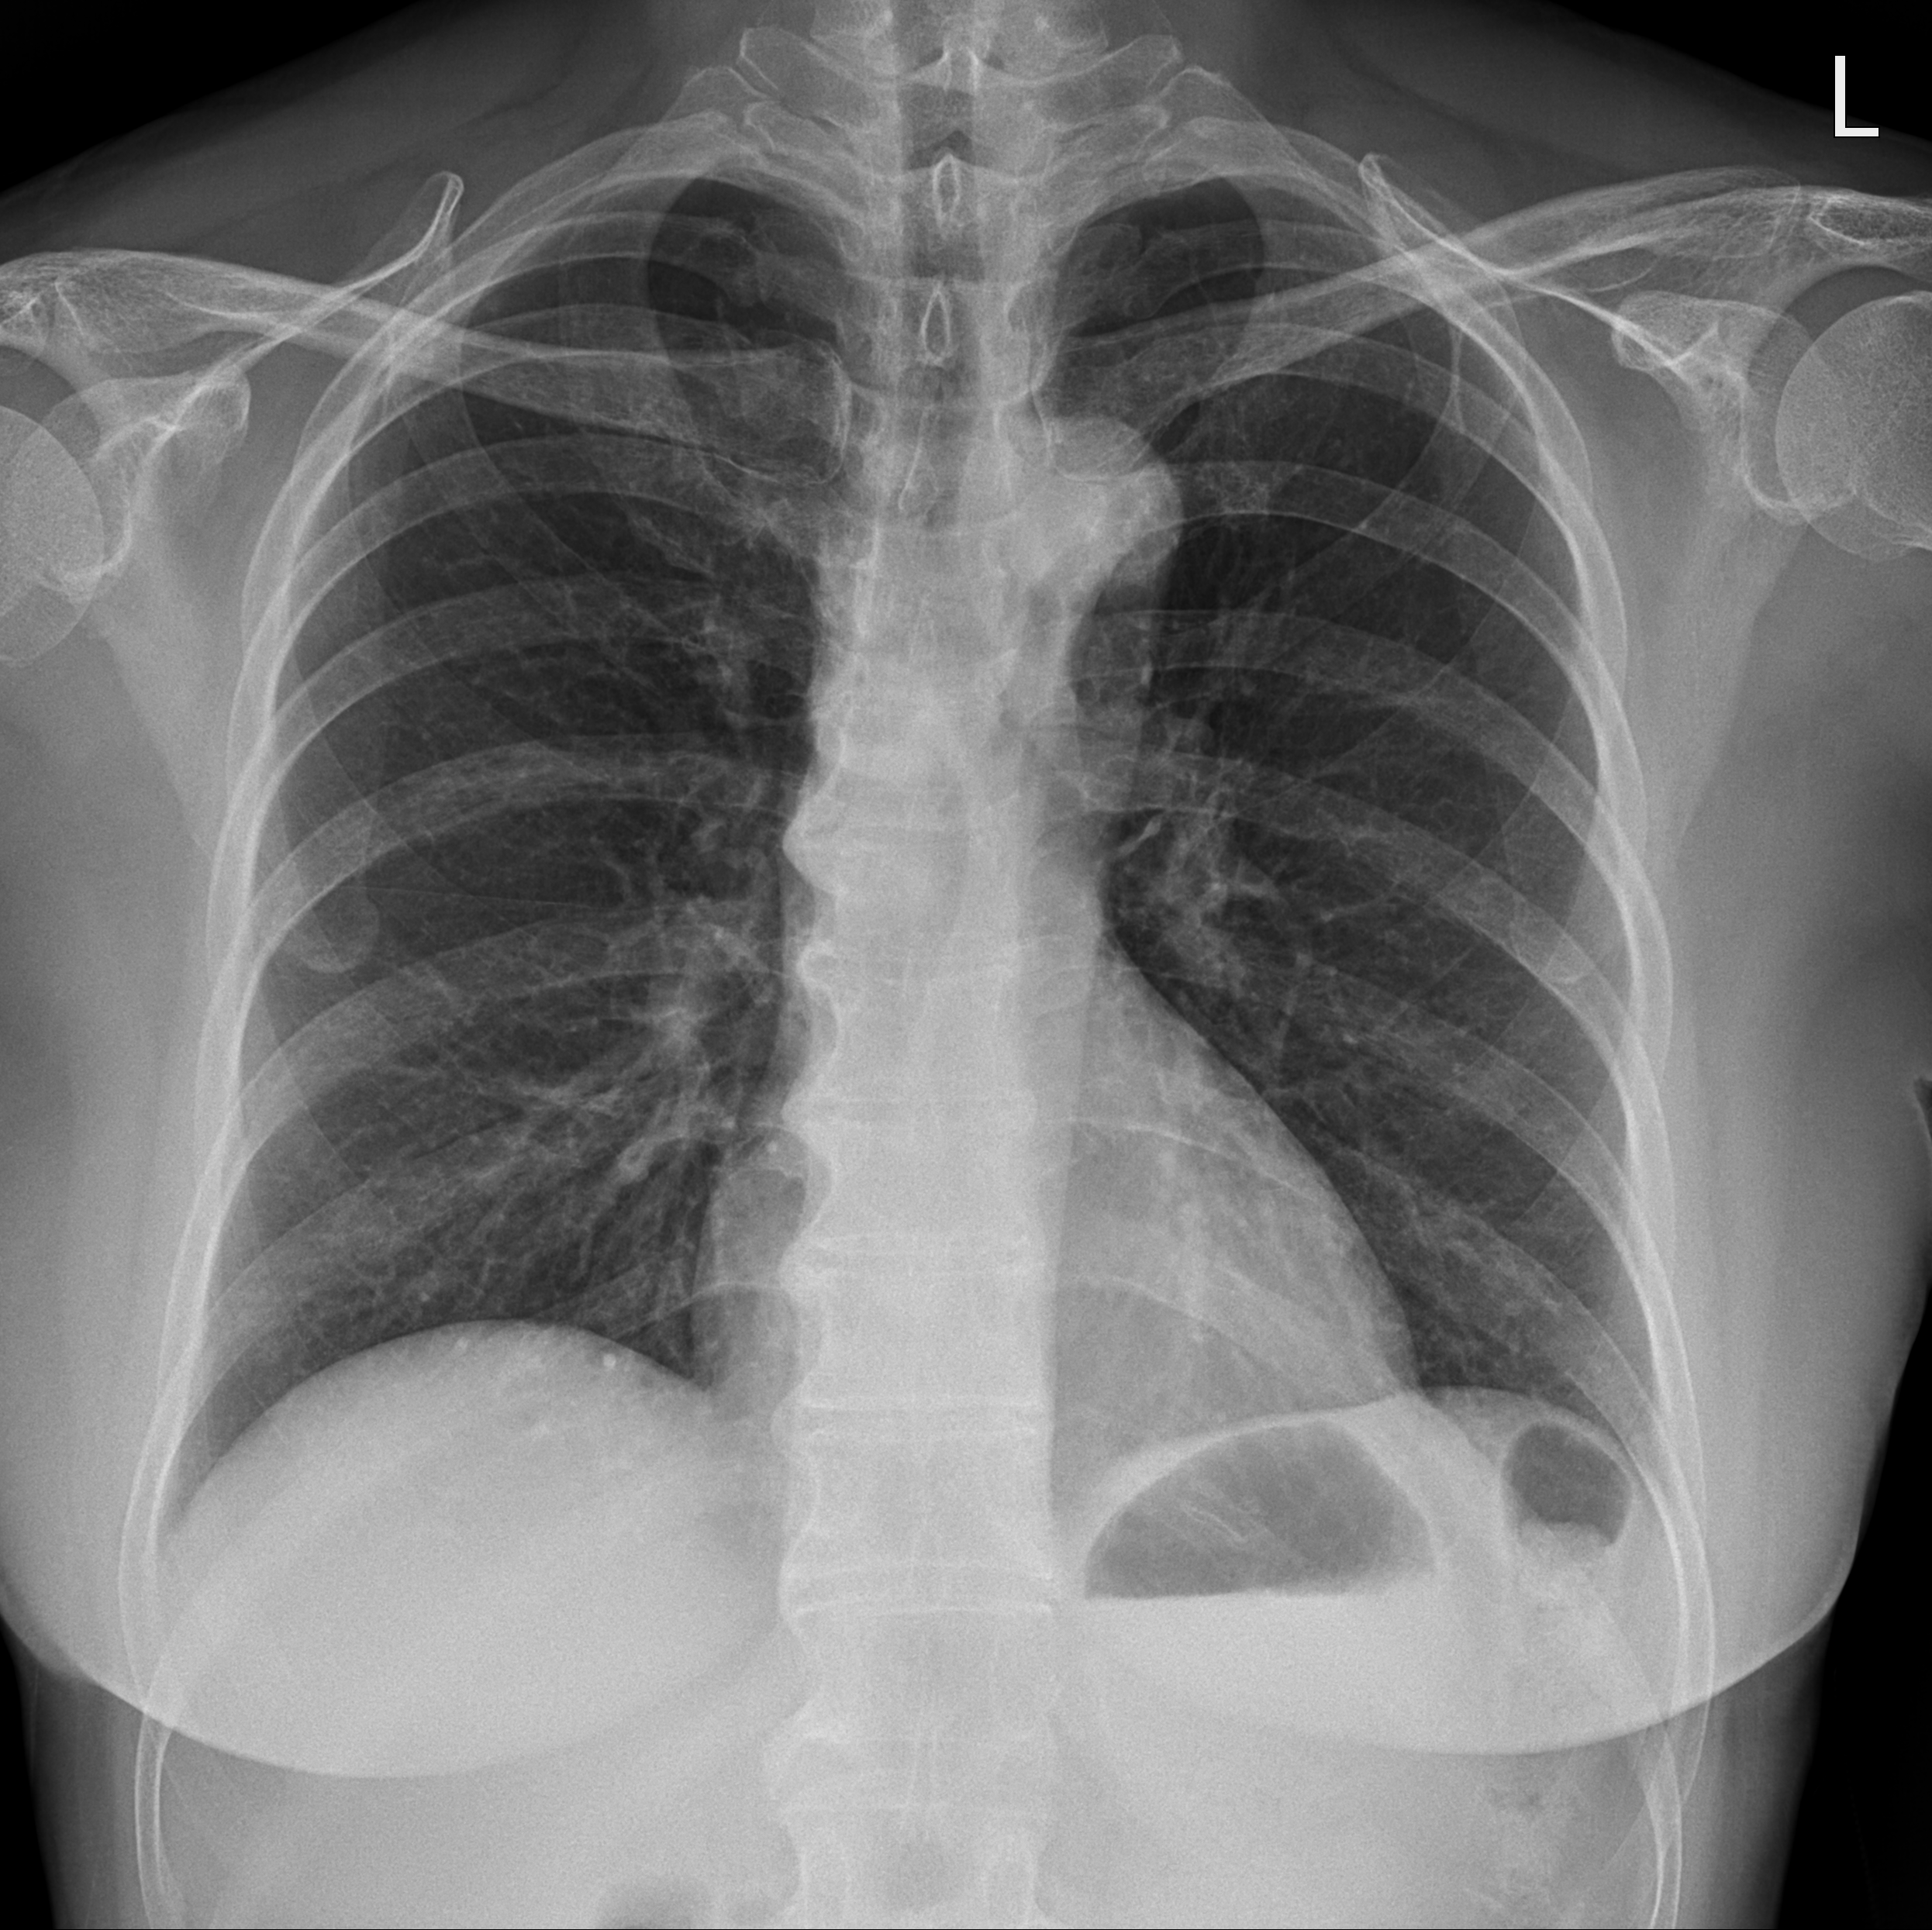

이물의 위치를 확정할 수 없으므로, 목부터 식도, 위장까지 확인하기 위해 흉부 x ray와 함께 경추 x ray(앞뒤와 측면)를 함께 촬영하였다.

예상과는 달리 chest PA, neck AP x ray 사진에서는 이물이 잘 보이지 않았다.